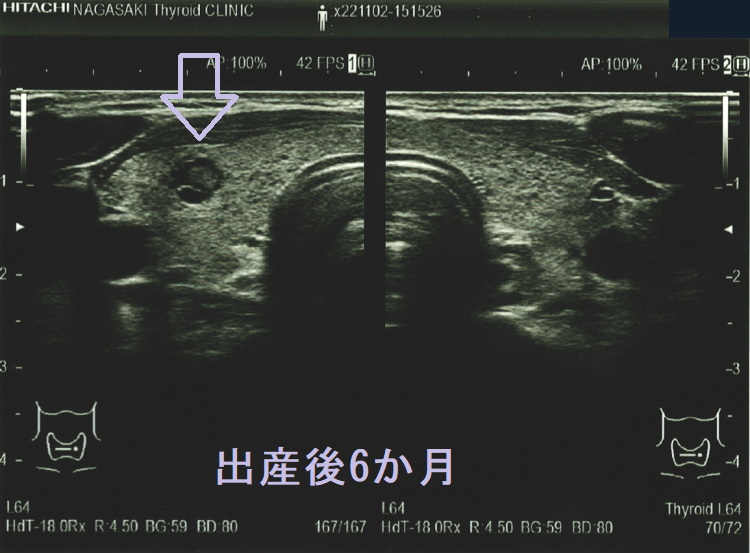

隈病院の統計では妊娠中、甲状腺微小乳頭癌の44.4%がサイズが増大するとのことです[Thyroid. 2014 May;24(5):840-4.]。もちろん、甲状腺刺激作用を持つhCGの影響が大きいと思われます[J Clin Endocrinol Metab. 1991 Oct;73(4):824-31.]が、あまり気持ちの良いものではありません。

アメリカ甲状腺学会の2017年ガイドラインでは、甲状腺微小乳頭癌の女性は妊娠中、甲状腺超音波(エコー)検査を妊娠前期・中期・後期に計3回受けることを推奨しています[Thyroid. 2017 Mar;27(3):315-389.]。

妊娠前の甲状腺超音波(エコー)検査ではなかったのに、出産後に甲状腺微小乳頭癌が見つかるケースがあります。甲状腺刺激作用を持つhCG[J Clin Endocrinol Metab. 1991 Oct;73(4):824-31.][Obstet Gynecol. 1990 May;75(5):775-8.]が、隠れていた甲状腺乳頭癌細胞の増殖を促進した可能性が考えられます。